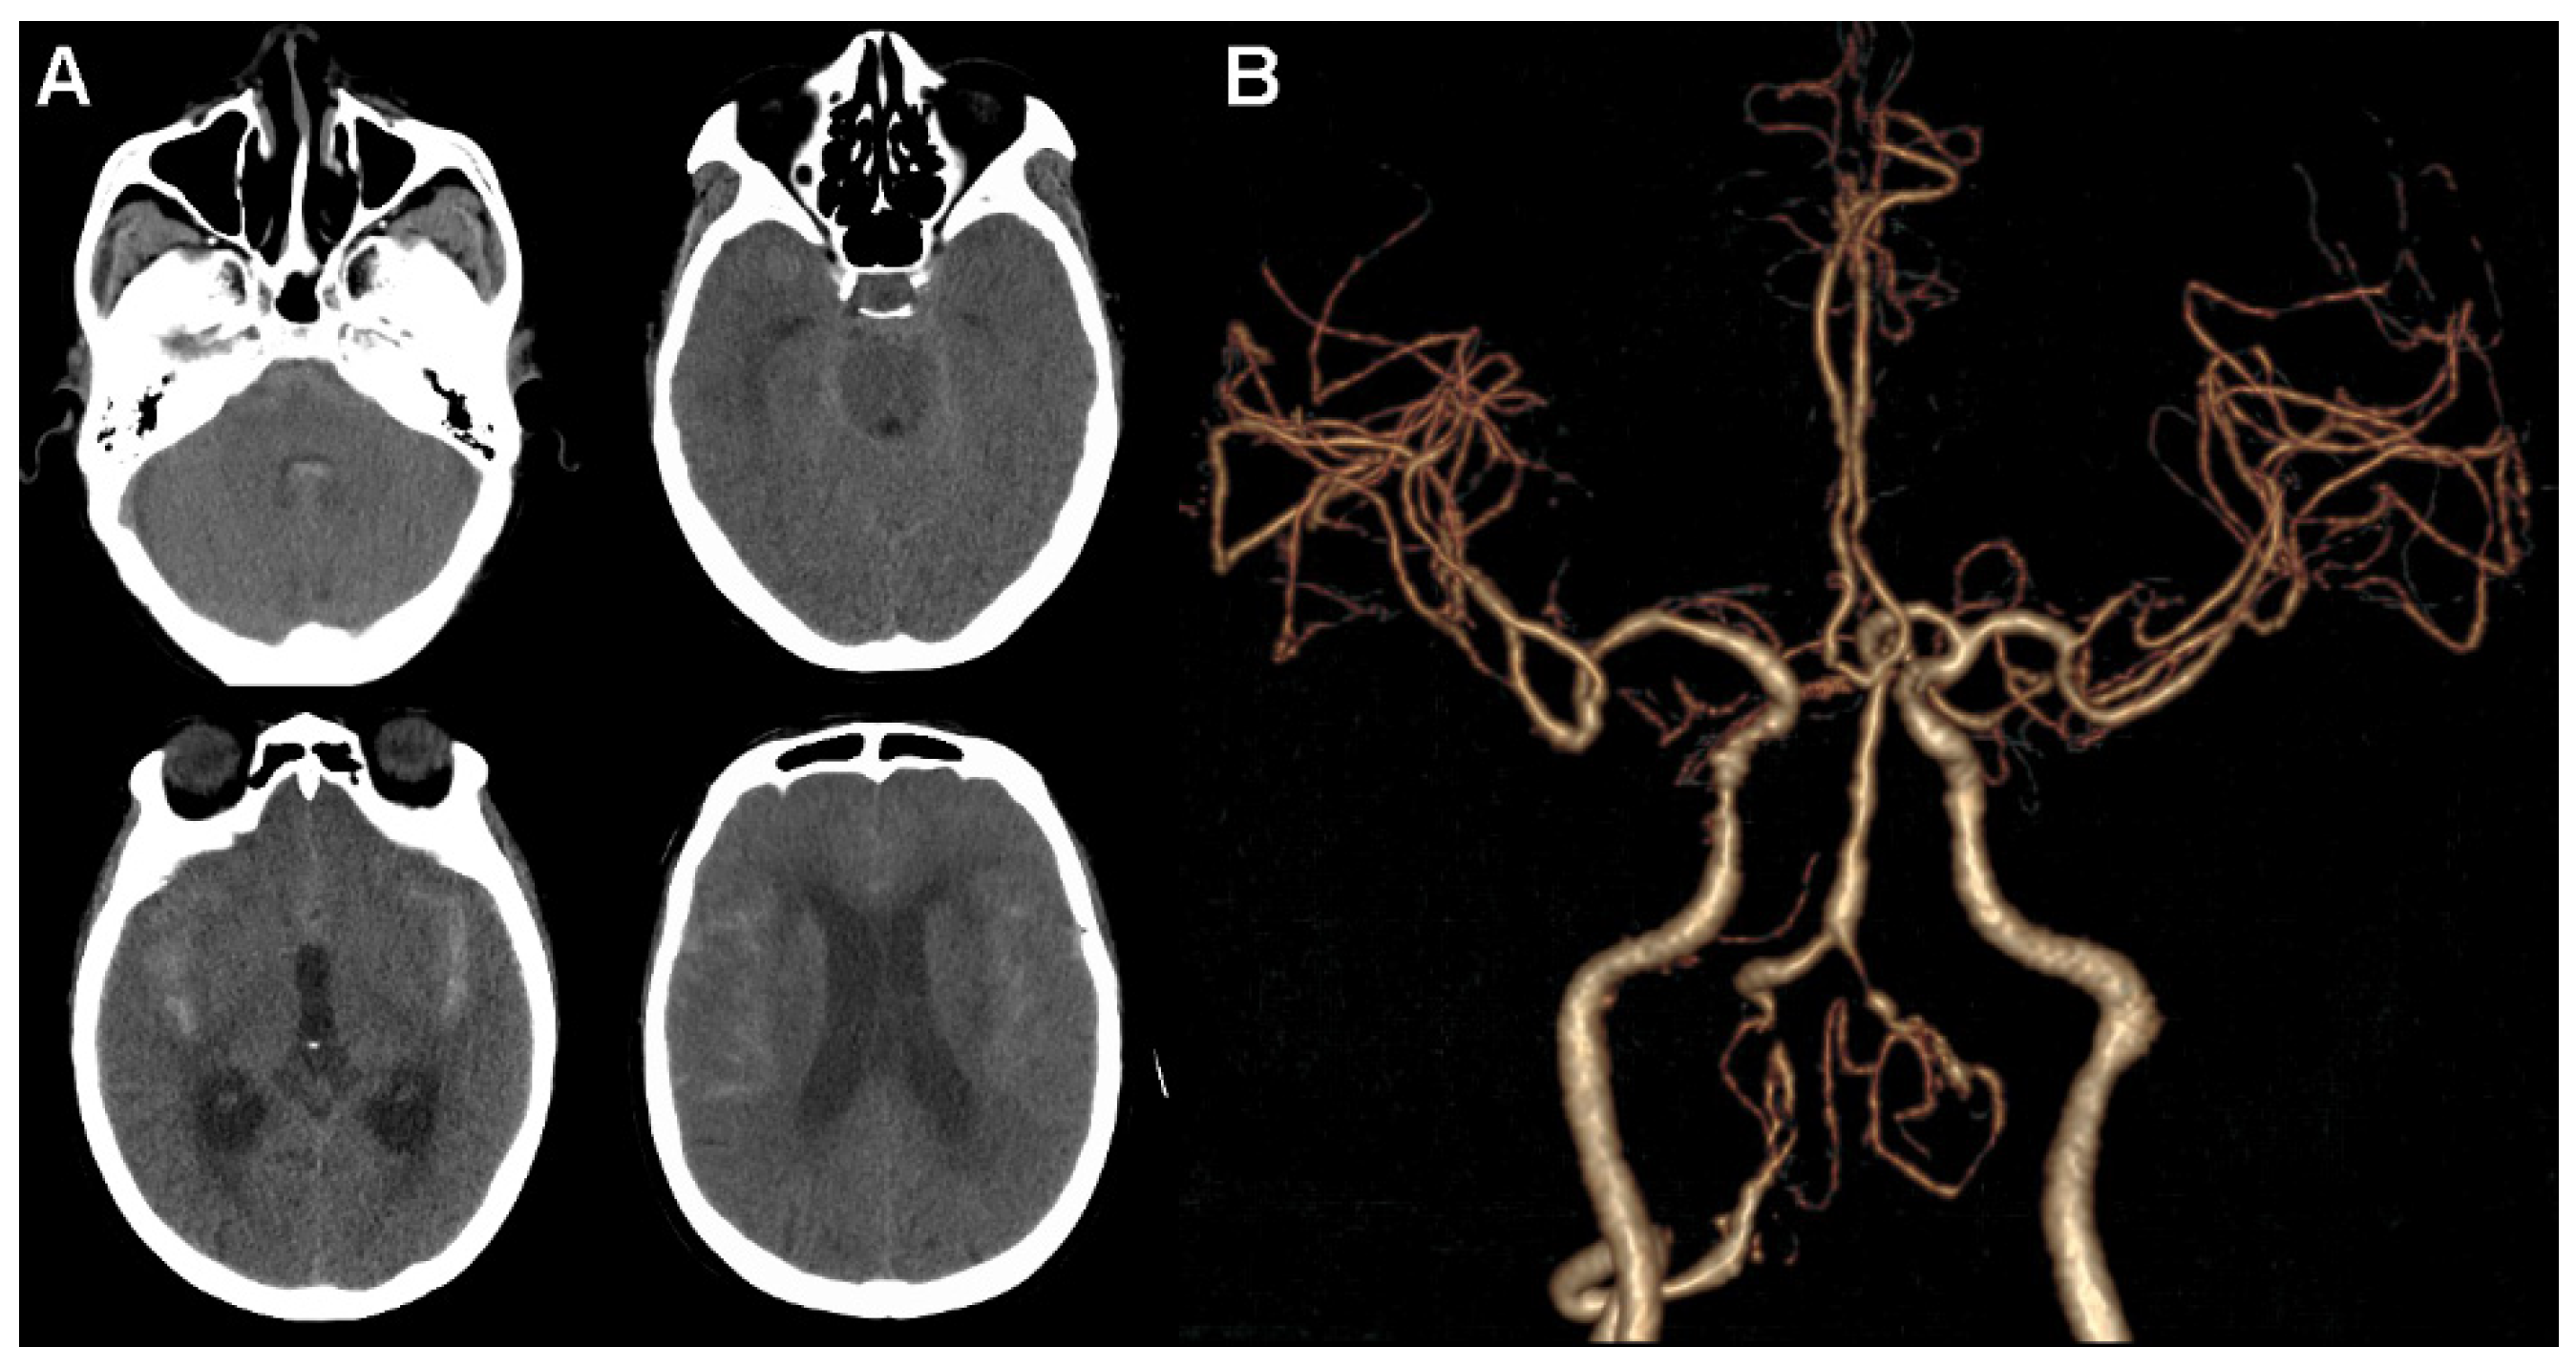

A 68-year-old woman with an unremarkable family history complained about a sudden onset of severe headache. She was admitted to the emergency department in our institution on the 1 March 2022, and a physical examination found lethargy and nuchal rigidity, suggesting a possible rupture of the intracranial aneurysm. An urgent cranial computed tomographic angiography (CTA) scan was performed, with the presence of SAH distributed mainly in the suprasellar, sylvian fissure, and prepontine cisterns, as well as in the fourth ventricle. Accordingly, the Hunt and Hess grade was 3. It also showed slight hydrocephalus with signs of ventricular dilation. However, there was no aneurysm or other vascular malformations in the intracranial arteries. Only irregular tandem stenosis or cerebral vasospasm in the intracranial segment of VA and right internal carotid artery were observed (Figure 1).

Figure 1.

Head computed tomographic angiography scan. (A) Extensive subarachnoid hemorrhage is shown in axial images. (B) No obvious aneurysm or other vascular malformations in intracranial arteries are observed.